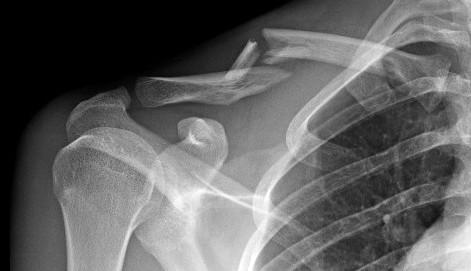

This person was pitching for softball when all of a sudden something didn't feel quite right and her arm was hanging a funny way... Which of the following best describes this shoulder injury?

Dislocation

This person was at football practice and dropped a barbell as they were doing bench presses on heavy weight day. Which of the following best describes this clavicle injury?